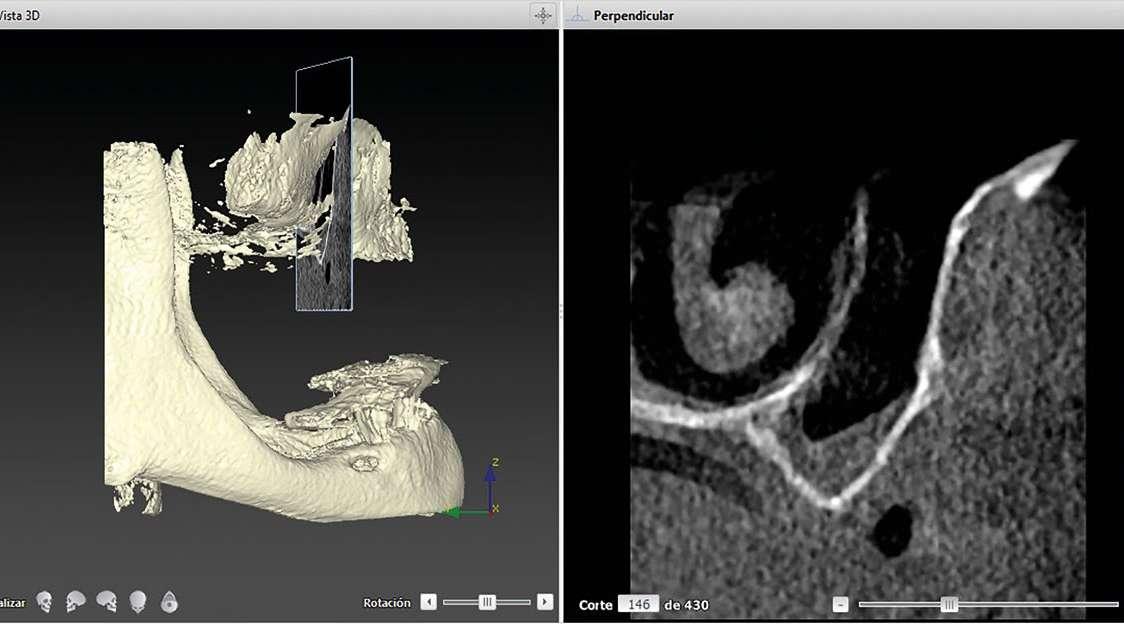

La exploración radiográfica es fundamental no sólo para el diagnóstico del caso, sino para la planificación

del mismo. Lo primero que deberemos valorar es si los senos maxilares están neumatizados y hasta qué punto lo están. En caso de elevación de seno deberemos descartar que el ostium esté obliterado o no, pues es causa de complicaciones postoperatorias o incluso una contraindicación absoluta si se acompaña de un engrosamiento anómalo de la membrana sinusal.

Se ha demostrado de la misma forma, que la anatomía del seno, grosor y calidad del hueso rema-

nente influye en el tiempo y calidad de la formación ósea1. Así un seno sin altura ósea, ancho y de paredes sin hueso esponjoso, tendrá peores resultados y mayores tiempos de maduración. Deberemos tenerlo en cuenta para el abordaje que realicemos del caso como explicaremos posteriormente. En el caso que exponemos, se observó un seno con escaso hueso esponjoso, nula altura ósea y ancho en sentido vestíbulo palatino. La peor situación posible (Figura 3).

caso clínico

Si bien la altura en la zona anterior premaxila es suficiente, la anchura previa era de menos de 2 mm con un hueso bastante cortical (Figura 4). Por lo que deberemos valorar una mezcla con gran componente de hueso autólogo.

La medición del CBCT con modelos mediante el software DTX nos permite saber el tamaño de las membranas previamente a la cirugía (3 membranas 30*40).